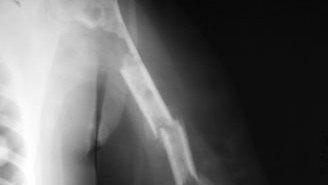

В данной статье рассказывается о сроках заживления сломанной руки. Описываются способы ускорения процесса выздоровления. Виды переломов руки Чтобы определить, сколько времени заживает перелом руки, необходимо знать вид травмы и степень повреждения костей. Переломы руки могут произойти в следующих местах: плечо; предплечье – лучевая или локтевая кость; суставы – плечевой, локтевой, лучезапястный; кисть руки и пальцы. Кроме локализации, переломы различают по отношению к кожным покровам. При закрытом переломе кожные покровы остаются целыми, и такой перелом заживает значительно быстрее...

Перелом - это повреждение кости, которое приводит к нарушению ее целостности. Переломы могут быть открытыми или закрытыми, полными или неполными, а также могут иметь различные формы и местоположения в костях тела. Переломы могут происходить в результате травмы, падения, аварий и других причин. Симптомы перелома включают боль, отек, синяки, нарушение функции, а также возможно деформация кости. Лечение переломов может включать ношение гипса или других фиксирующих устройств, физиотерапию, хирургическое вмешательство и реабилитацию...